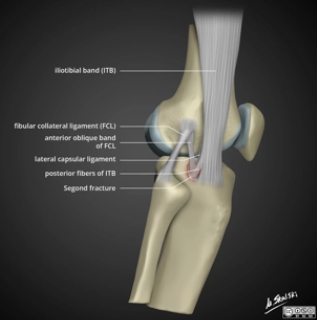

“雷声小雨点大”的恐怖骨折

“雷声小雨点大”的恐怖骨折!